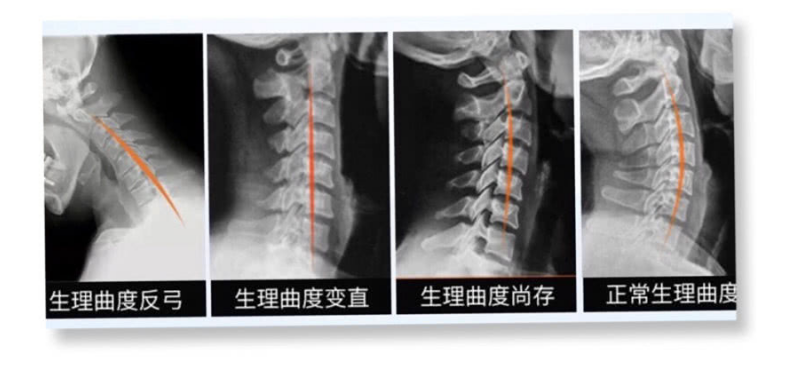

全職麻麻這兩年,陪娃帶娃總是低著頭,好不容易寶寶睡了有自己時間了忍不住低頭玩手機,結果我天天脖子痛的厲害,去醫院診斷為頸椎反弓,正常頸椎的生理曲度應該是向前彎曲,如果長期不良姿勢會導致曲度變直然后是反弓,我當時覺得很嚴重問醫生咋辦。醫生淡淡的說:沒有辦法現在大家頸椎強直的,反弓的太多了,最普遍和嚴重的原因就是長期的低頭玩手機。

生理曲度的改變醫生們也沒有辦法,不可能做手術吧,一般會建議你做康復治療,就是經常去醫院做頸部牽引之類得長期堅持不然效果不大,那么到底怎么才能改變回正常的生理曲度呢?